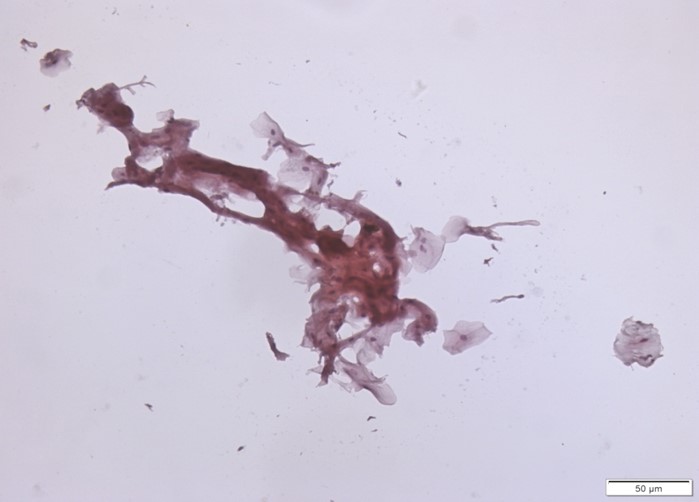

Consideram-se amostras insuficientes para análises quando há escassez de material, pois o tempo despendido para a interpretação da lâmina seria incompatível com a conclusão de avaliação (Figura 5). Amostras de lesão bucal maligna, como por exemplo, de Carcinoma Espinocelular, geralmente são examinadas para fins científicos de pesquisa (usados como controles positivos); uma vez que se há suspeita de neoplasias malignas já instaladas a biópsia e o exame histopatológico são imperativos.

Exemplo de amostra insuficiente

Exemplo de mostras de lesão bucal maligna